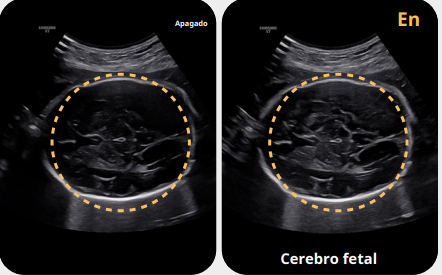

ClearVision™

ClearVision™ es un sistema de filtrado avanzado que reduce el ruido y mejora el contraste de los bordes en imágenes 2D en tiempo real. Permite obtener imágenes más nítidas y precisas, optimizando la interpretación de exámenes obstétricos y ginecológicos y facilitando diagnósticos rápidos y confiables.